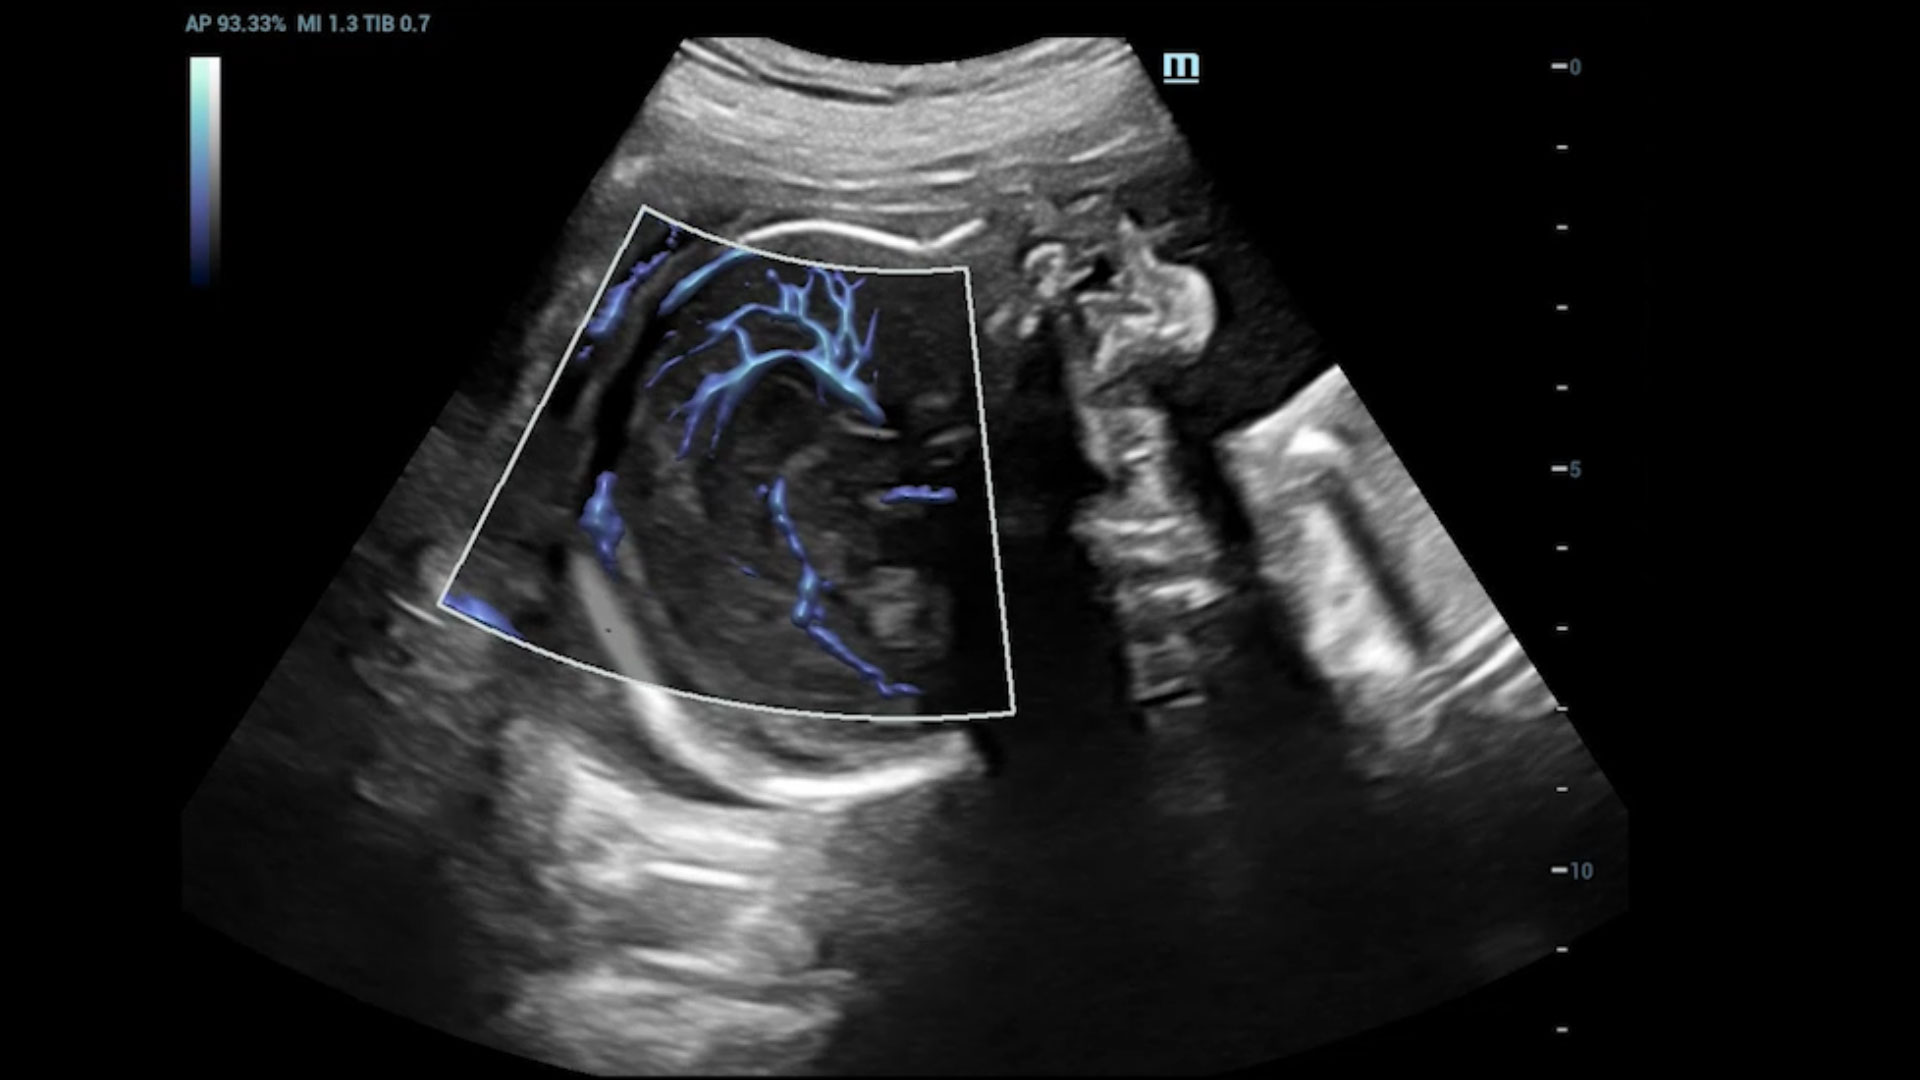

UMA (Ultra-Micro Angiography)

The innovative technology breaks the bottlenecks of traditional Doppler imaging. With ultra-high spatial resolution and flow sensitivity, it allows detecting super-subtle and super-slow flow perfusions, thereby extending the clinical application of qualitative and quantitative ultrasound evaluation in fetal brain, kidney, placenta, endometrium, ovary, etc.

UMA - fetus renal flow